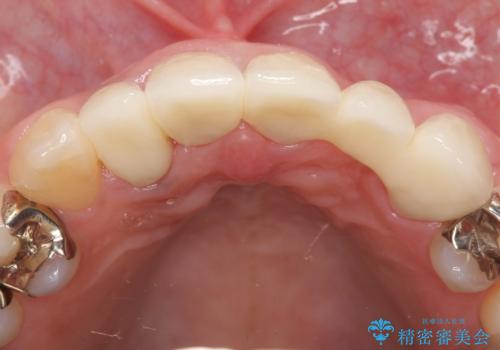

- 昔入れた被せ物と歯茎の間の隙間が気になると来院された方の症例です。

右上1、2番目の歯と左上1、2、3、番目の歯のブリッジを除去し、オールセラミッククラウンによる補綴を行うことで見た目を改善しました。

今回用いたオールセラミッククラウンはジルコニアフレームという白い素材の上にセラミックを盛っているため、審美性が非常に高いのが特徴です。

また、ジルコニアは人工ダイヤモンドの材料にも使われているほど高い強度を持っており、そのためオールセラミッククラウンは審美性だけでなく、奥歯やブリッジの補綴も可能とするクラウンです。